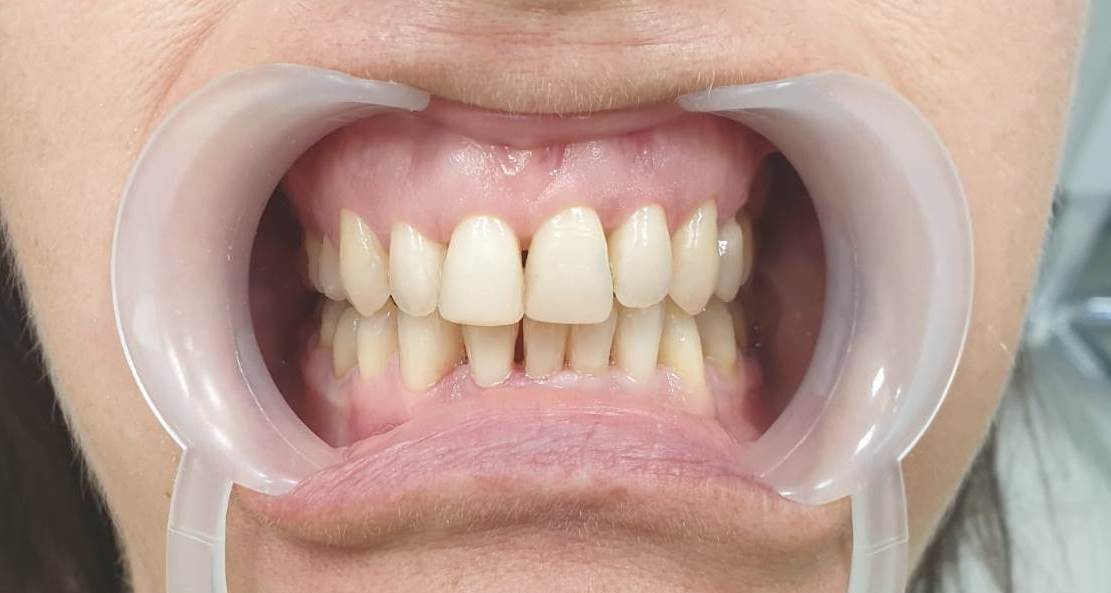

Pacjent przed zabiegiem

Pacjent po zabiegu flow injection - dolny łuk zębowy

Pacjent przed zabiegiem

Pacjent po zabiegu flow injection - górny łuk zębowy